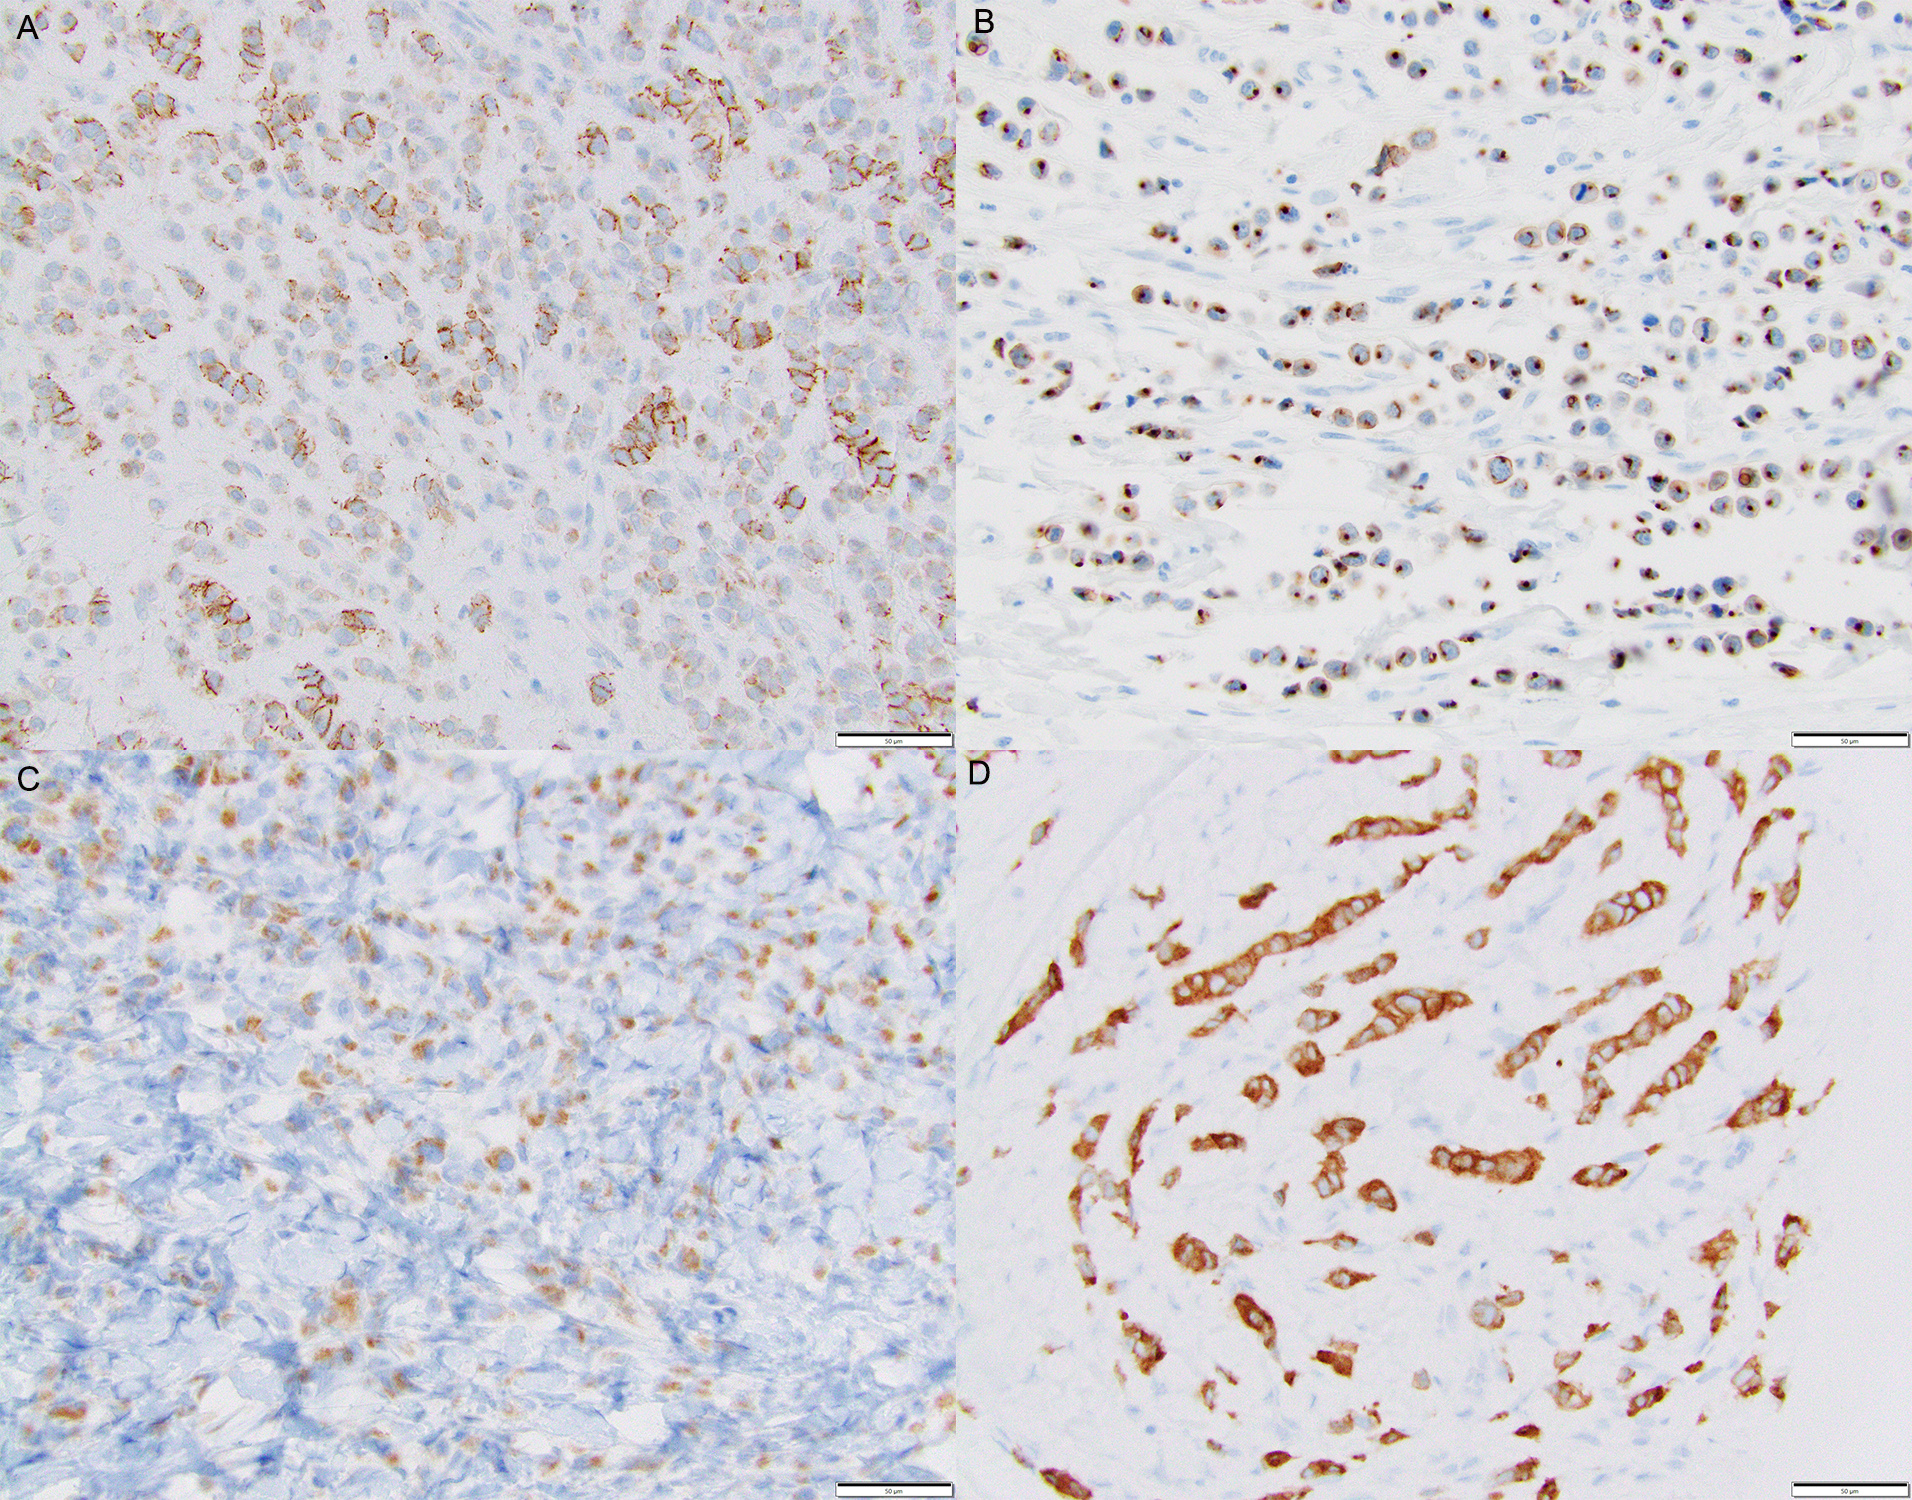

A diagnosis of ILC can be confirmed using immunohistochemical staining for E-cadherin which frequently shows loss of reactivity in the tumor cells. At the current time, the world health organization (WHO) classification of tumors, 5th edition does not recommend performing E-cadherin immunohistochemical staining for breast tumor classification but the reality is that 50% of the institutions do use it in a variety of ways. If E-cadherin IHC is not routinely used, then there is a potential to misclassify tumors, promotes use of non-standard terminology and significant inter-observer variability. Prior studies have also shown that subtyping of breast cancer as ILC achieves almost perfect agreement with a pre‐defined reference standard, if assessment is supported by E‐cadherin IHC.1 However, if E-cadherin is routinely performed but not appropriately optimized and validated, then again the tumors can be misclassified. Moreover, if the pathologists are unaware of “aberrant” reactivity of E-cadherin, tumors will still be misclassified. Absence of circumferential membranous E-cadherin reactivity should be classified as “aberrant” as it often correlates with CDH1 gene mutations (Figure 1).

To improve standardization of ILC diagnosis, we have been routinely performing E-cadherin to confirm first time ILC diagnosis at our institution since 2004-2005. However, in doing so routinely, we have encountered tumors that morphologically resemble ILC on hematoxylin and eosin (H&E) stain slides but demonstrate circumferential membranous reactivity for E-cadherin. We have always wondered if these tumors follow a clinical course similar to ILC or IDC and whether they demonstrate characteristic CDH1 mutations. We labeled these tumors lobular-like invasive mammary carcinoma (LLIMCa or LiMCa) for our study and compared and contrasted their clinical-pathologic features with grade matched IDC and ILC. We also performed an exploratory molecular analysis of 7 LiMCa and 7 ILC to understand the molecular mechanisms that results in this morpho-immunohistologic appearance.

Our study further clarifies the terminology used in describing breast carcinomas with ambiguous morphology (ductal versus lobular) and classification based on E-cadherin, and other cadherin-catenin junction protein like p120 and beta-catenin staining (Table 1).2 LiMCa appears to be distinct from the other described subtypes. Even after using numerous immunohistochemical stains for classification, some tumors are still difficult to categorize and it is reasonable to label them as invasive mammary carcinoma with indeterminate differentiation (ductal versus lobular). Targeted sequencing, CDH1 promoter methylation and in rare cases whole genome sequencing of such cases can provide further insight.

In summary, we describe the clinical-pathological features of LiMCa – a low to intermediate grade mammary carcinoma that shows single cell infiltrating growth pattern (like classical-type lobular carcinoma) but shows retained membranous expression of E-cadherin and other related proteins (p120 and beta-catenin). These tumors lack the characteristic CDH1 mutations but a proportion of them show CDH1 promoter methylation. Their clinical-pathological features are intermediate between ILC and IDC. The prognosis is related to tumor stage and multivariable prognostic model of Magee Equation score.3 Using LiMCa terminology will help us learn more about these peculiar tumors.